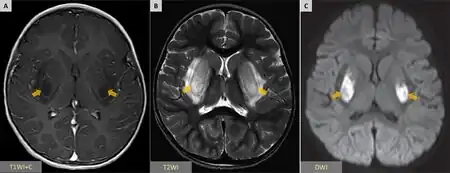

People with HUS commonly exhibit the symptoms of thrombotic microangiopathy (TMA), which can include abdominal pain,[13] low platelet count,[14] elevated lactate dehydrogenase LDH, (a chemical released from damaged cells, and which is therefore a marker of cellular damage)[15] decreased haptoglobin (indicative of the breakdown of red blood cells)[15] anemia (low red blood cell count), schistocytes (damaged red blood cells),[14][15] elevated creatinine (a protein waste product generated by muscle metabolism and eliminated renally),[16] proteinuria (indicative of kidney injury),[17] confusion,[13] fatigue,[18] swelling,[19] nausea/vomiting,[20] and diarrhea.[21] Additionally, patients with aHUS typically present with an abrupt onset of systemic signs and symptoms such as acute kidney failure,[14] hypertension (high blood pressure),[18] myocardial infarction (heart attack),[22] stroke,[13] lung complications,[22] pancreatitis (inflammation of the pancreas),[20] liver necrosis (death of liver cells or tissue),[14][18] encephalopathy (brain dysfunction),[18] seizure,[23] and coma.[24] Failure of neurologic, cardiac, renal, and gastrointestinal (GI) organs, as well as death, can occur unpredictably at any time, either very quickly or following prolonged symptomatic or asymptomatic disease progression.[5][6][14][17][25]

The consumption of platelets as they adhere to the thrombi lodged in the small vessels typically leads to mild or moderate thrombocytopenia with a platelet count of less than 60,000 per microliter.[42] As in the related condition TTP, reduced blood flow through the narrowed blood vessels of the microvasculature leads to reduced blood flow to vital organs, and ischemia may develop.[10] The kidneys and the central nervous system (brain and spinal cord) are the parts of the body most critically dependent on high blood flow, and are thus the most likely organs to be affected. However, in comparison to TTP, the kidneys tend to be more severely affected in HUS, and the central nervous system is less commonly affected.[43]

- ↑ 33.0 33.1 Mansour, Moustafa A.; Khalil, Dyana F.; Hasham, Mohab A.; Youssef, Ahmed; Rashad, Mohamed; Awadallah, Muhammad; Ali, Hassan (June 2023). "Hemolytic uremic syndrome with central nervous system manifestations, a case report and literature review". Radiology Case Reports. 18 (6): 2268–2273. doi:10.1016/j.radcr.2023.02.035. ISSN 1930-0433.